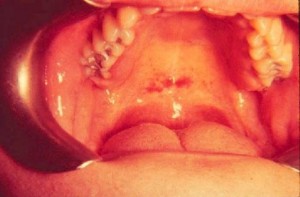

Мононуклеоз инфекционный (моноцитарная ангина) — вирусное инфекционное заболевание. Инкубационный период 6-15 дней. Мононуклеоз инфекционный имеет острое начало и течение. Шейные лимфатические узлы увеличены в виде цепочки и по заднему краю грудино-ключично-сосцевидной мышцы, малоболезненны. Отмечается лихорадочное состояние. В полости рта развивается ангина, а затем язвенно-некротический стоматит. Типичным для мононуклеоза инфекционного является изменение крови: лейкоцитоз до 18 тыс., количество моноцитов увеличивается до 70%, тромбоциты снижаются до 40 тыс., появляются атипичные мононуклеары, СОЭ умеренно повышена.